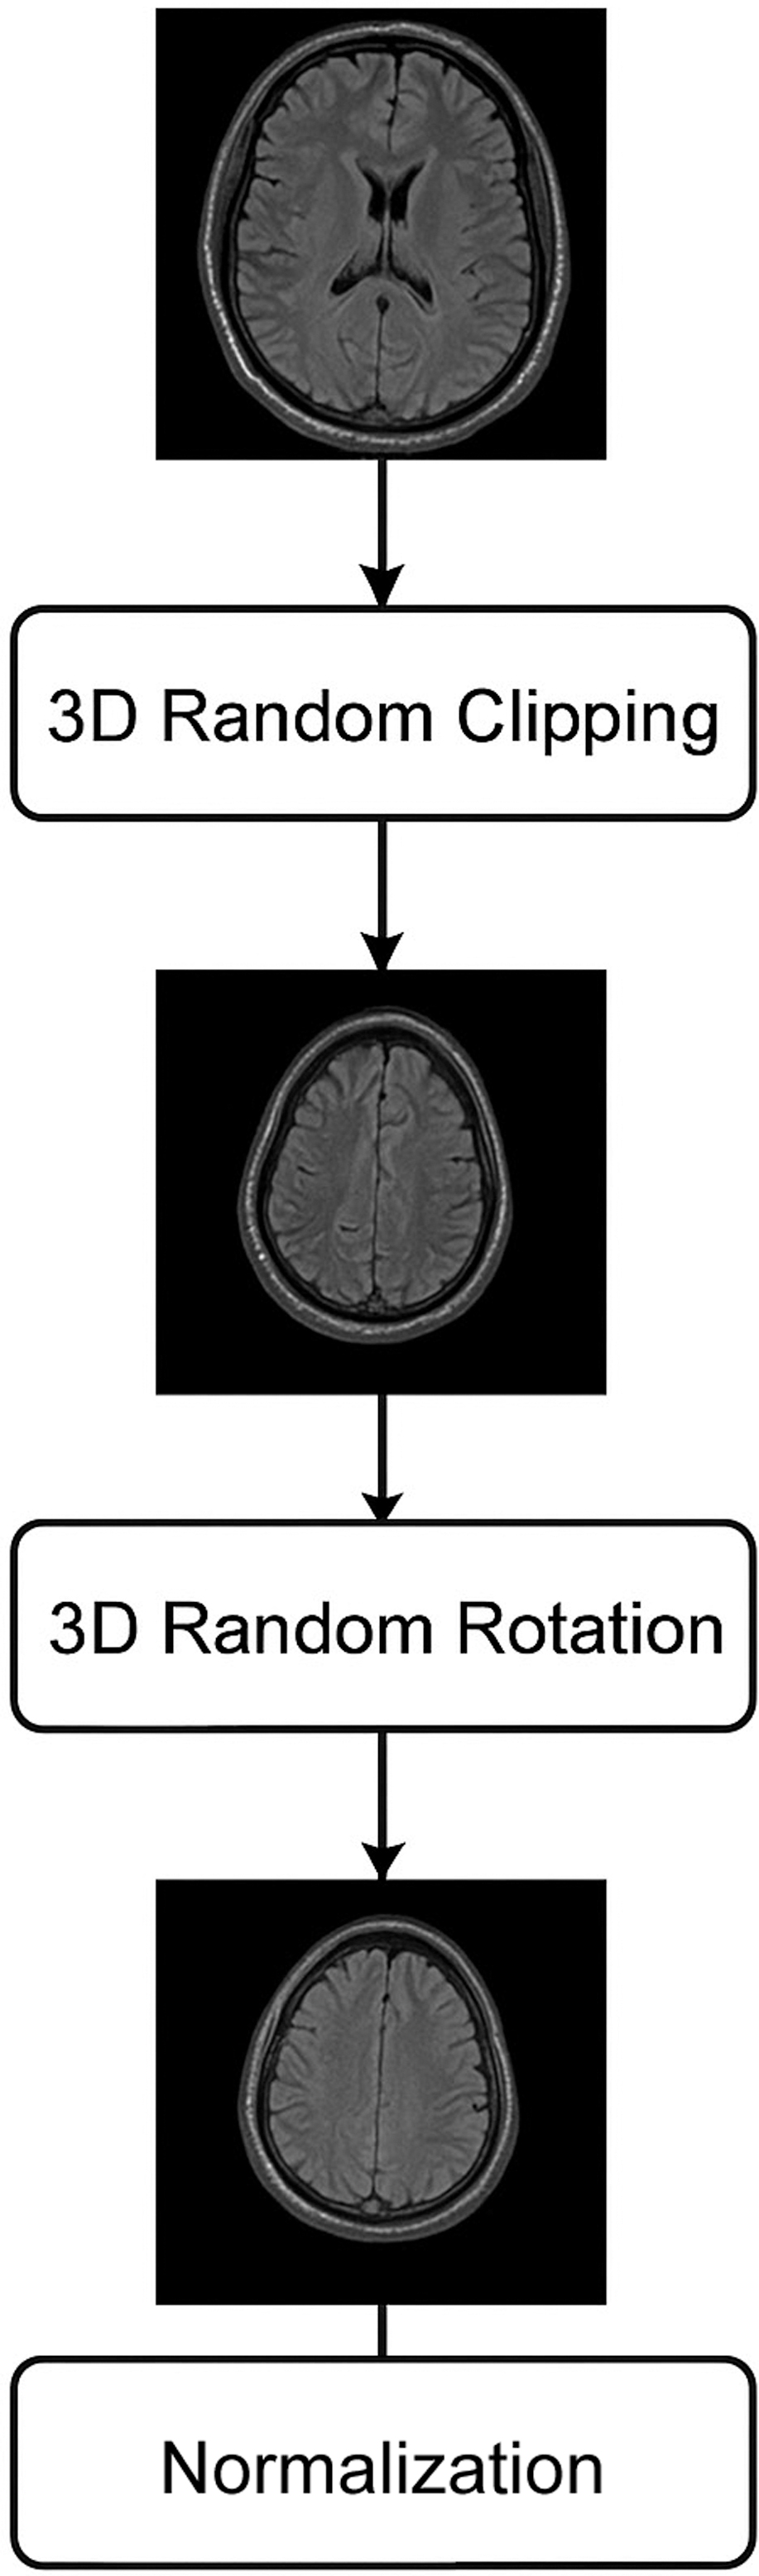

This approach employs a randomization scheme as a preprocessing step for images; this could guarantee that the deep learning perfect keeps its excellent generalization presentation even after extensive training. To ensure that the input photos vary throughout training epochs, we use the same random seeds for each batch of images. In order to achieve generalization, it is helpful to learn the picture characteristics of several modes in the same brain. 3D random clipping, 3D random rotation, and 3D normalization are the preprocessing picture methods shown in Fig. 6.

Fig. 6. Preprocessing steps applied to MRI scans.

where the mean value is μ and the standard deviation is σ. After that, the MRI scan (240, 240, 155) is randomly divided into a matrix (144, 144, 128) using the 3D random clipping technique. The reduced picture is rotated by an angle using the 3D random rotation technique. U(−10, +10):Where S represents the distribution that is uniform. The picture is mirrored in all three dimensions (height, width, and depth) using random mirror processing. In order to increase the deep neural network’s performance and generalizability, we use these picture-enhancing algorithms to expand the training dataset.